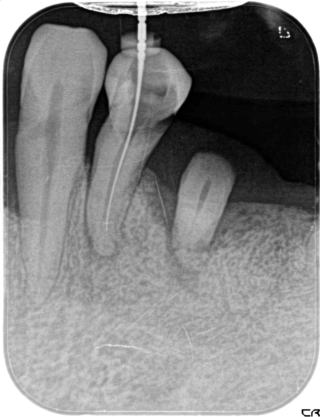

歯内療法:根管の湾曲:神経はまっすぐとは限らない